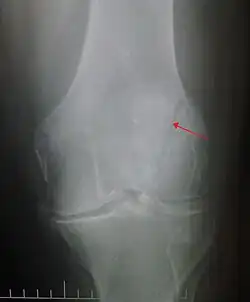

Transverse fracture of patella -

The patella can break in various ways depending on the way it is injured, and into two or more pieces.[1] Types include transverse, the most common, with one fracture line;[5] marginal; osteochondral; and the rare vertical type, or stellate, where a direct compression force gives rise to a comminuted pattern.[5][7] Patella fractures can be further classified as displaced, where the broken ends of bone do not line up correctly and separate by more than 2mm, or undisplaced and stable where pieces of bone remain in contact with each other.[1][7] If fragments of patella bone stick out from the skin it is known as an open patella fracture, and closed if the overlying skin is intact.[1]